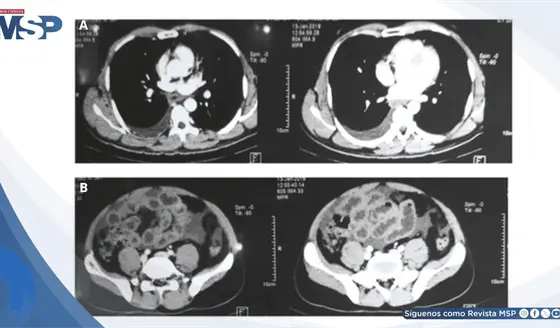

A pesar del tratamiento intervencionista exitoso mediante embolización, evolucionó con complicaciones de hipertensión portal severa, presentando descompensación aguda con hemorragia digestiva alta y choque hipovolémico.